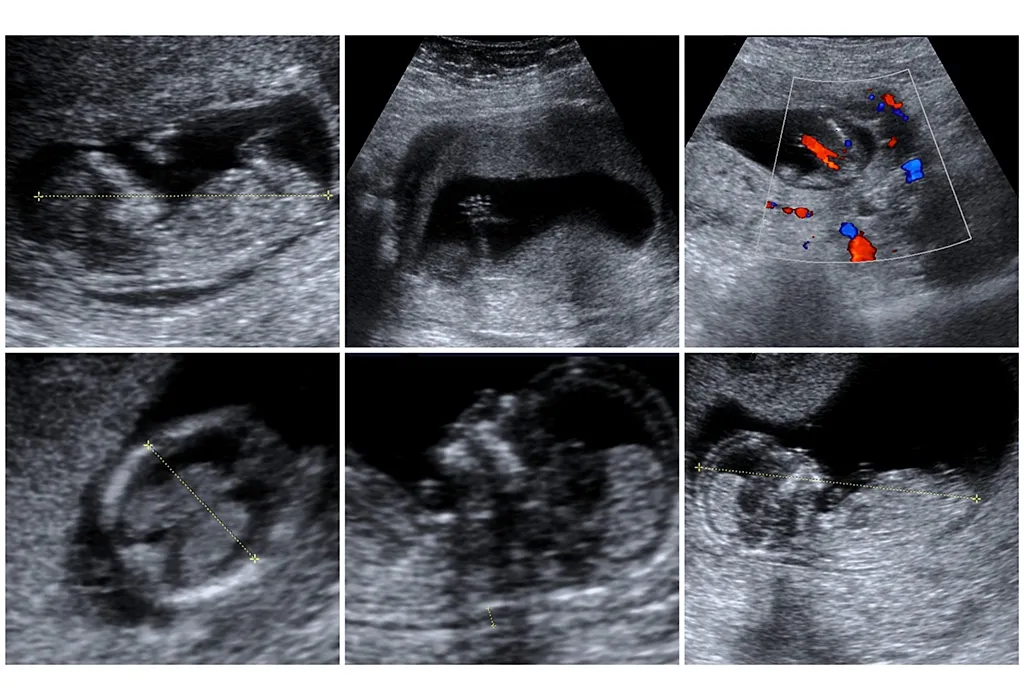

Doppler sonography or foetal Doppler ultrasound is a technique that is used to measure the flow of blood through the umbilical cord. It checks if the flow to all the parts of the body, including your baby’s brain and heart, is normal. This shows whether the baby is getting all the required nutrients and oxygen or not. Doppler sonography is used to diagnose different problems related to pregnancy.

The person who carries out the scan (or the sonographer) puts a gel on your tummy and moves the transducer, a hand-held device, over it. This device sends sound waves into your womb. These waves bounce off your baby’s blood flow through the circulatory system and umbilical cord. This bouncing back is used to check how your baby is doing.

The standard ultrasound equipment is used to get a picture of the blood vessels and the surrounding organs. The Doppler sound is made into a graph by a computer, which shows the speed and the direction of blood flow through the vessels.

Colour Doppler

Why Is Doppler Sonography Done?